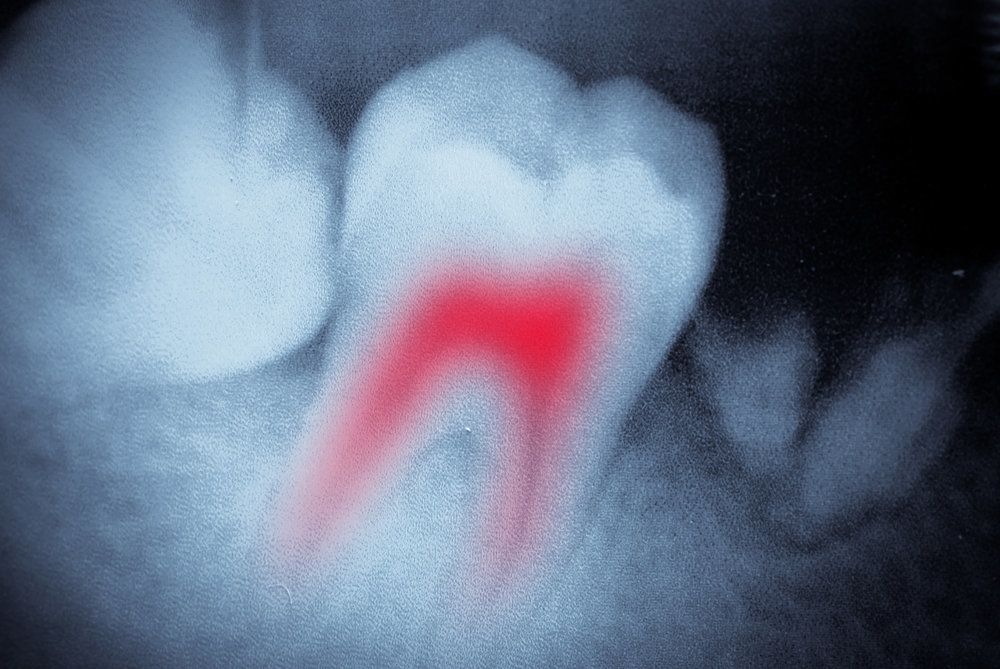

Root Canal Treatment

Root canal therapy can treat advanced tooth decay, helping you avoid the need for extraction. Dr. Goodman will remove bacteria, infected tissue, preserving the healthy exterior with a dental crown. Our gentle root canal treatment can ease discomfort and restore the health and function of your smile.